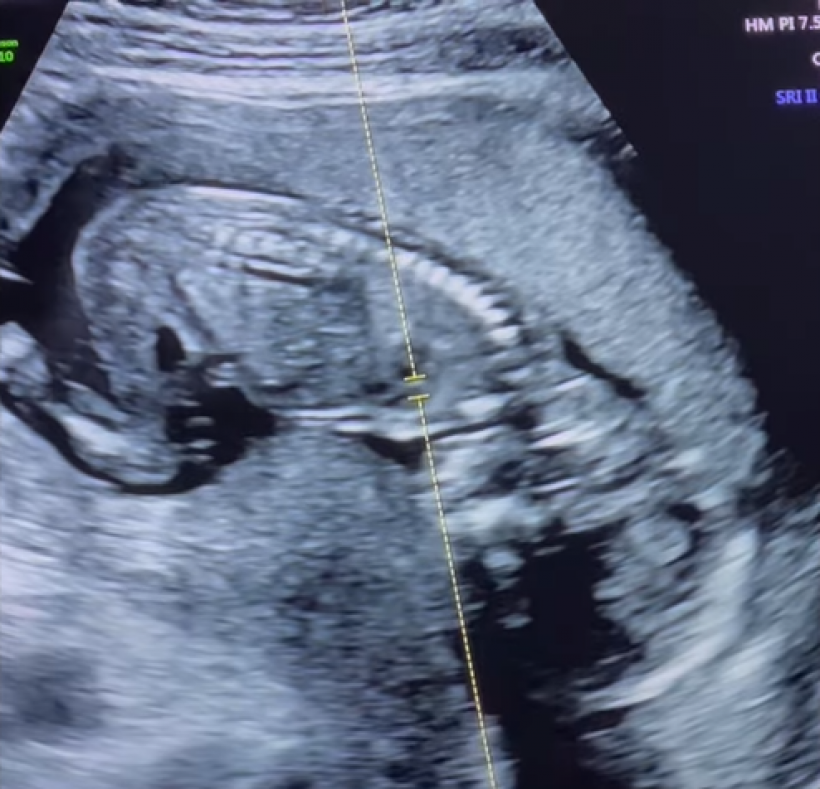

ล่าสุด ดา โพสต์คลิปอัลตร้าซาวด์ พร้อมเเคปชั่นว่า “ขอบคุณคำอวยพรวันเกิดจากทุกคนนะ…ปีนี้อยากจะบอกว่า “ดาได้ของขวัญวันเกิดที่พิเศษที่สุดแล้วนะ” 🎁🥹 THE BEST BIRTHDAY PRESENT EVER! ❤️”

Cr_ig: daendorphine